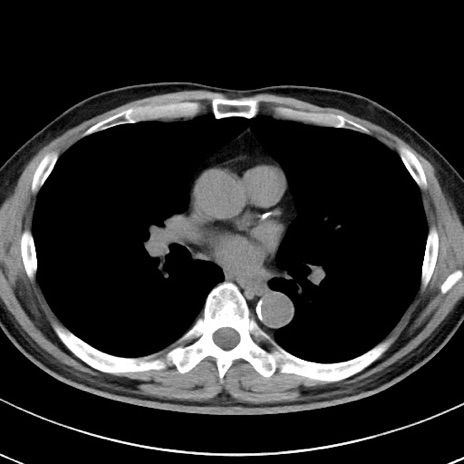

【腹部TIPS】症例29 参考症例 CT(横断像)

症例

70歳代男性